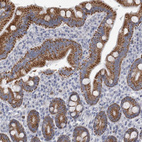

Immunohistochemistry analysis in human kidney and lymph node tissues using HPA026443 antibody. Corresponding AGMAT RNA-seq data are presented for the same tissues.